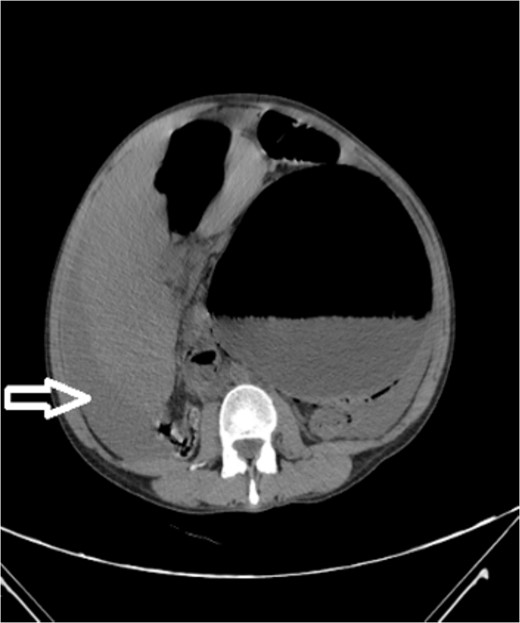

Upon admission to our hospital, the patient’s physical examination revealed hypotension (87/52 mmHg) and tachycardia (150 bpm), along with marked diffuse abdominal tenderness and guarding. Laboratory investigations indicated a hemoglobin level of 7.1 g/dl, a white blood cell count of 14.5 × 103 μl, and a platelet count of 202 × 103 μl. An abdominal CT scan without contrast showed an enlarged ectopic spleen measuring 18 cm in the right abdominal area, a distended stomach, a moderate volume of hemoperitoneum, and significant intra-abdominal fluid accumulation. CT findings are shown in Figs 1–3. Based on these findings, the patient was immediately transferred to the operating room.

Noncontrast axial CT scan of the abdominopelvic area showing a left-sided pelvic hematoma.